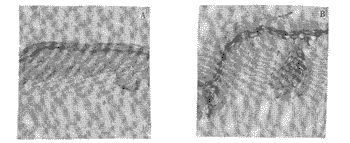

标本在跨膜培养系统中培养24h后,用HE染色显示,所培养的皮肤标本可保持完整的组织形态和结构。免疫染色发现,培养基中单纯培养24h,正常皮肤表皮棘细胞层中角蛋白16、17无明显表达或仅在颗粒层下呈微弱阳性(图1A)。单纯培养后,I型转谷酰胺酶在正常皮肤的表达和培养前基本相同,即仅在颗粒层呈线状阳性,棘细胞层呈阴性(图2A)。单纯培养前后,ICAM-1在正常的皮肤不表达(图3A),HLA-DR染色仅限于少数树枝状细胞呈阳性。而在培养基中加入IFN-γ刺激培养后,角蛋白17和I型转谷酰胺酶在正常皮肤棘细胞层均有强表达,染色呈强阳性(图1A和图2B)。角蛋白16的染色和单纯培养相比较,则无明显变化;ICAM-1和HLA-DR在IFN-γ的诱导刺激下,正常皮肤基底层和基底上层出现阳性(图3B)。上述结果表明,IFN-γ在皮肤器官培养条件下,可诱导表达一 系列与银屑病皮损相关蛋白分子(图4)。

图1 角蛋白17在正常皮肤组织中的表达

Fig1 Expression of keratin 17 in normal skin tissue(APAAP×82.5)

A:Cultured in medium as control;B:Cultured in medium with IFN-γstimulation.

图2 I型转谷酰胺酶在正常皮肤组织中的分布

Fig2 Distribution of transglutaminase type I in normal skin tissues(APAAP ×82.5)

A:Cultured in medium as control;B:Cultured in medium with IFN-γ stimulation.